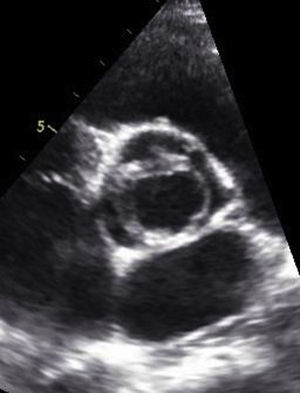

La ecocardiografía confunde a menudo la válvula aórtica unicúspide con la presencia de 2 cúspides, aunque la anatomía es fundamentalmente diferente20. La válvula aórtica bicúspide está caracterizada por la presencia de 2 comisuras de altura normal, las comisuras más altas se sitúan según los orificios coronarios correspondientes y solo la comisura hipoplásica tiene un nivel inferior a la normal. Por el contrario, la válvula aórtica unicúspide se caracteriza por una única comisura desarrollada normalmente y generalmente situada entre el seno no coronario y el coronario izquierdo. Ecocardiográficamente, el fenómeno característico es una abertura excéntrica en el eje corto (fig. 3). El mecanismo patogénico de la insuficiencia se produce por dilatación anular, por la displasia del velo de la coronaria derecha y por la posición anormal del velo derecho en la raíz aórtica. Generalmente, el jet de insuficiencia ecocardiográfico es central, mientras que en la válvula aórtica bicúspide el jet es excéntrico. La distinción es de gran importancia, puesto que la válvula aórtica unicúspide tiene una geometría diferente y requiere un enfoque distinto para su reparación. Es frecuente la presencia de calcificaciones en el velo coronario derecho; sin embargo, la extensión del calcio a los velos coronario izquierdo y no coronario crean una situación poco favorable para la reparación. Los componentes patológicos más importantes de la IA en casos de válvula aórtica unicúspide son la anomalía de las comisuras y la displasia del velo de la coronaria derecha, asociándose a menudo a una dilatación del anillo basal. En principio, la reparación sería factible si los velos están poco engrosados y no existen calcificaciones sobre el velo de la coronaria derecha21.